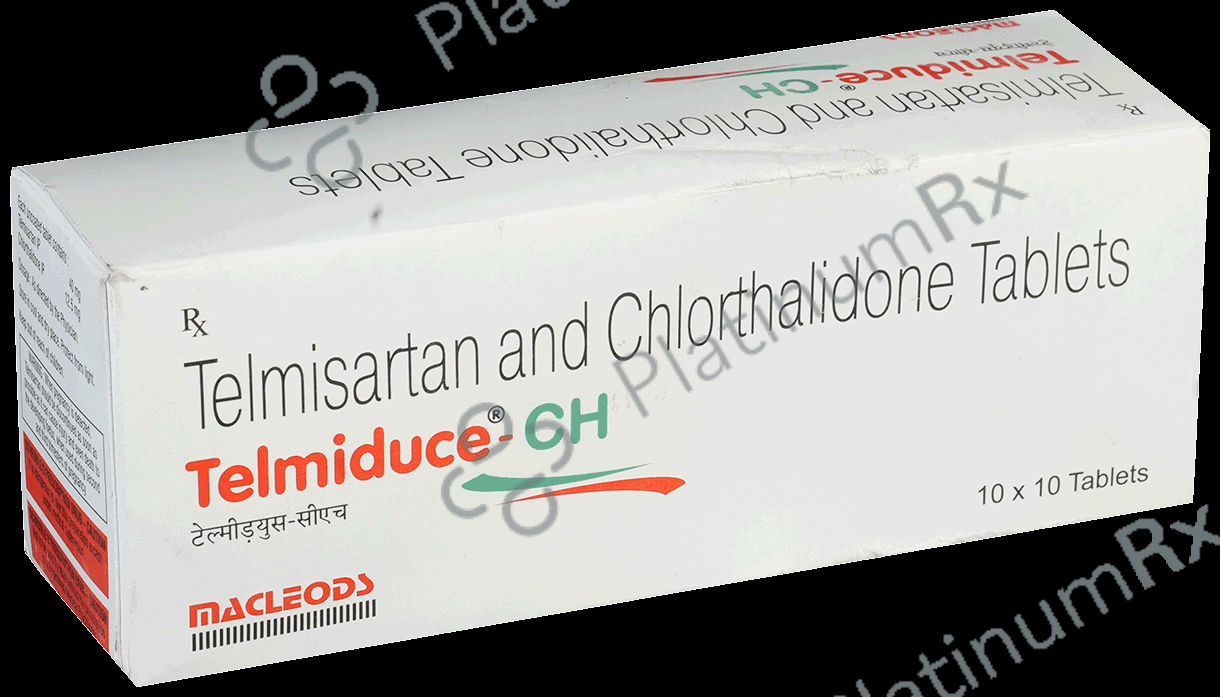

Telmiduce CH 40mg/12.5mg Tablet

Macleods Pharmaceuticals Pvt Ltd

Strip of 10 tablets

Telmiduce CH 40mg/12.5mg Tablet

Macleods Pharmaceuticals Pvt Ltd

Strip of 10 tablets

₹107.5

₹10.8 / Unit